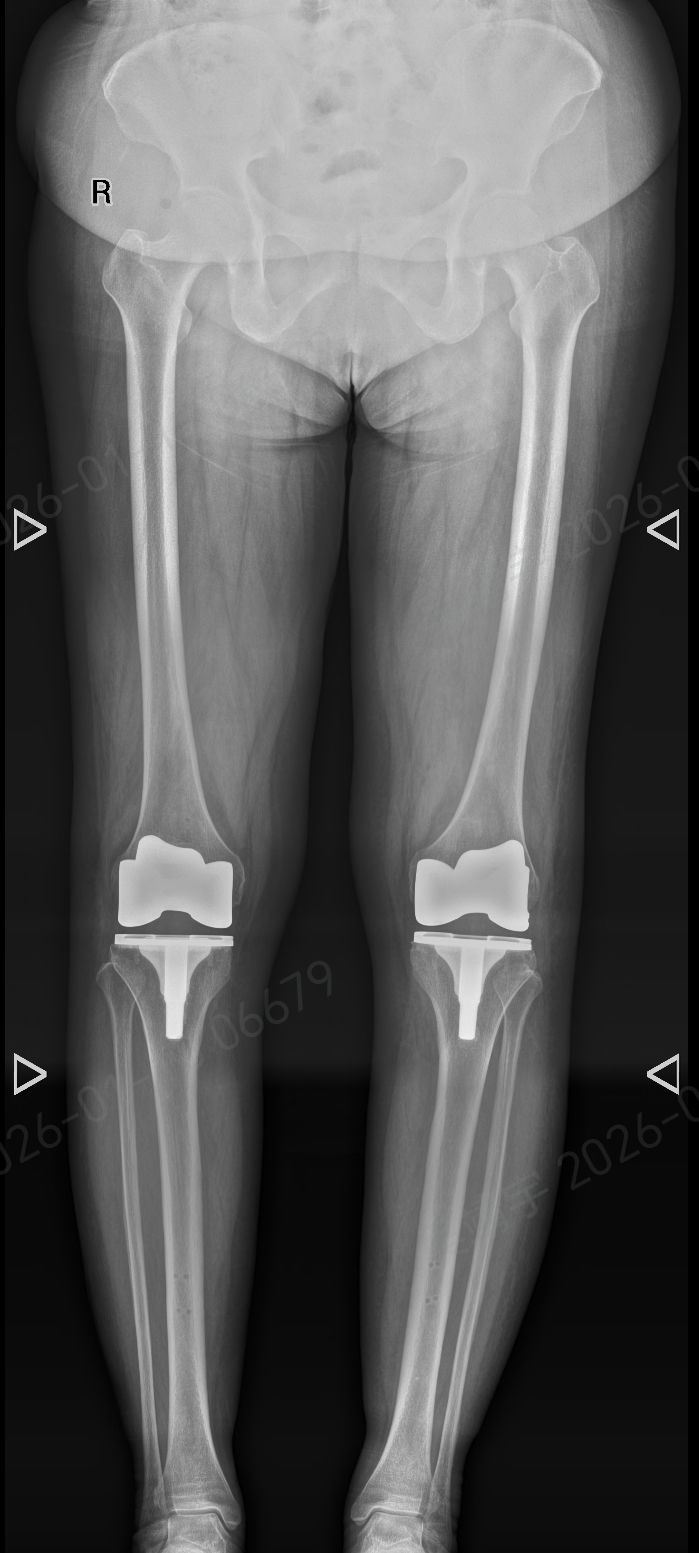

天玑机器人与手术团队密切配合,将外科临床经验与智能技术深度融合。相较于传统手术,此次机器人辅助手术在操作精准度、软组织保护等方面呈现显著优势,术中出血量更少,手术流程更优化。

手术结束后,张阿姨的膝关节畸形得到矫正,疼痛感明显改善。令人欣慰的是,她在术后次日便能自主站立,目前已顺利开展功能康复训练,逐步向正常行走目标推进。